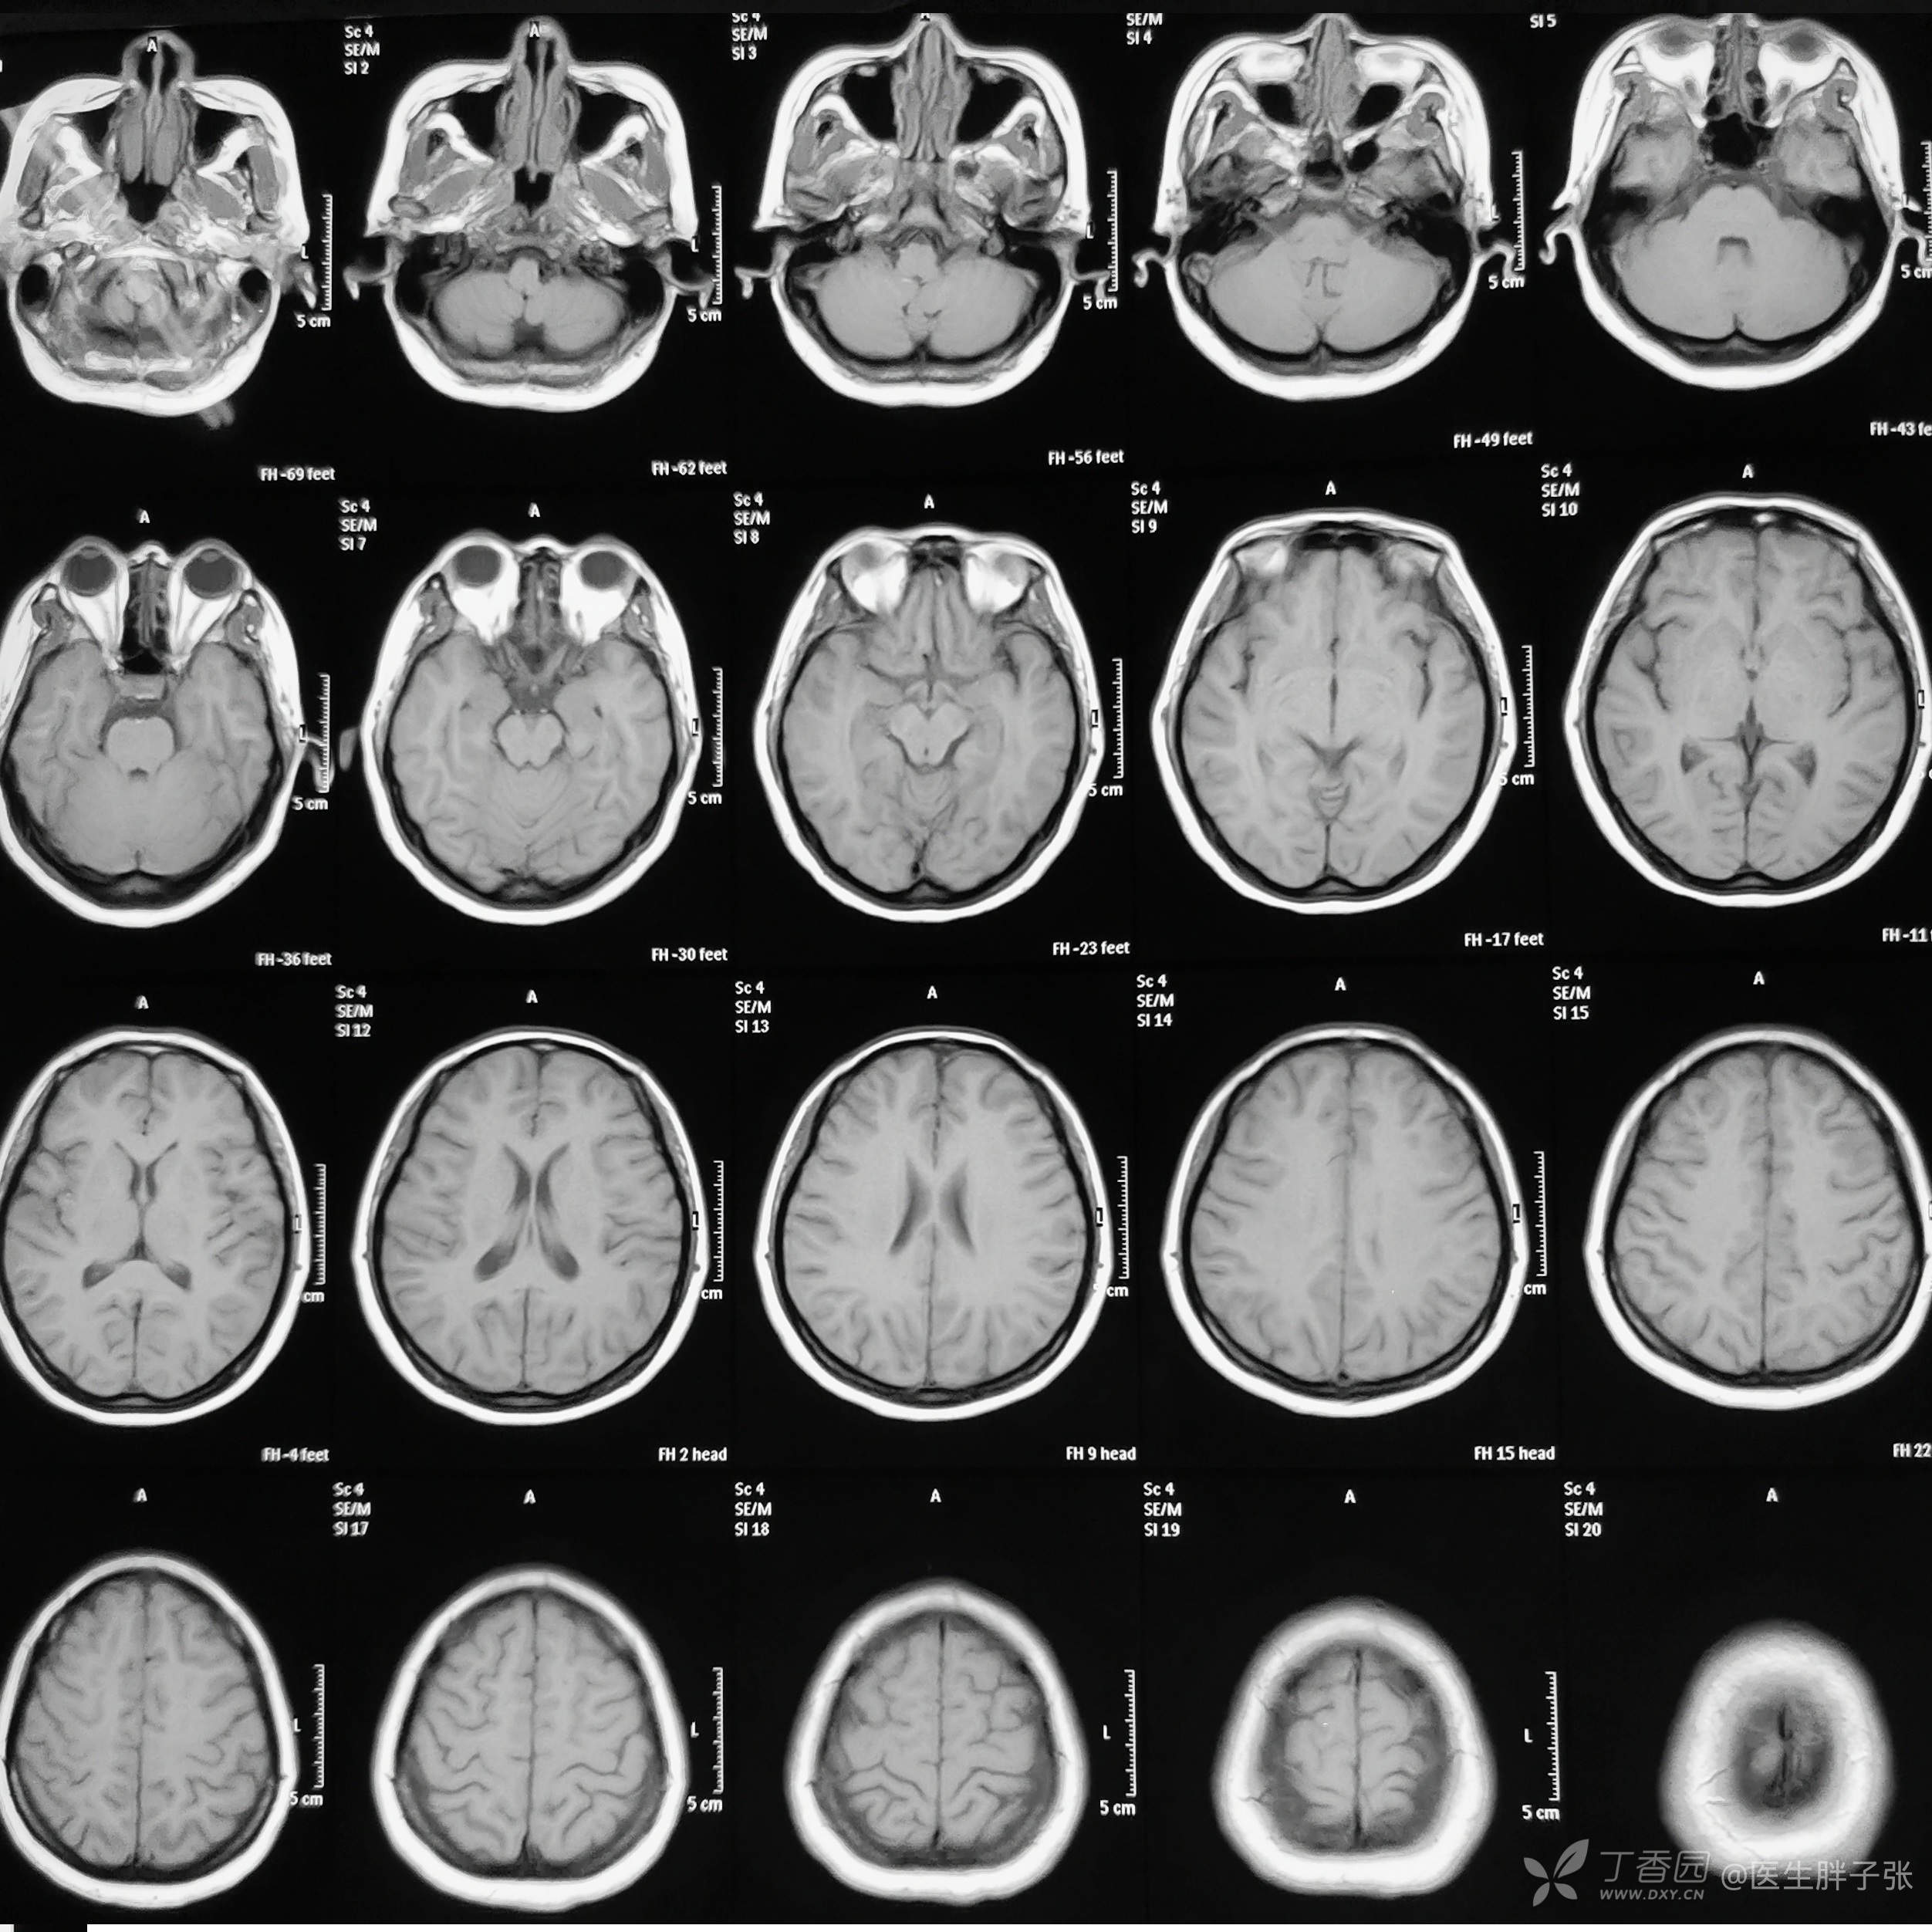

辅助检查:心电图示冠状静脉窦心率,V4、V5 T波改变。颅脑核磁:MRI平扫及MRA未见异常。右侧横窦、上矢状窦局部官腔充盈缺损,考虑静脉窦血栓可能性大,直窦、下矢状窦未见显示,先天发育异常可能性大。